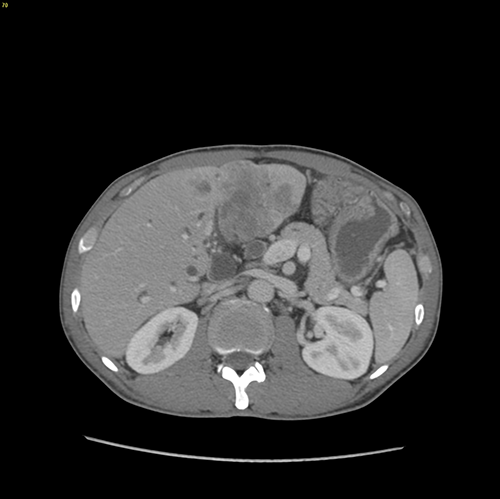

左肝癌并胆管癌栓---左半肝切除、胆管癌栓取出术